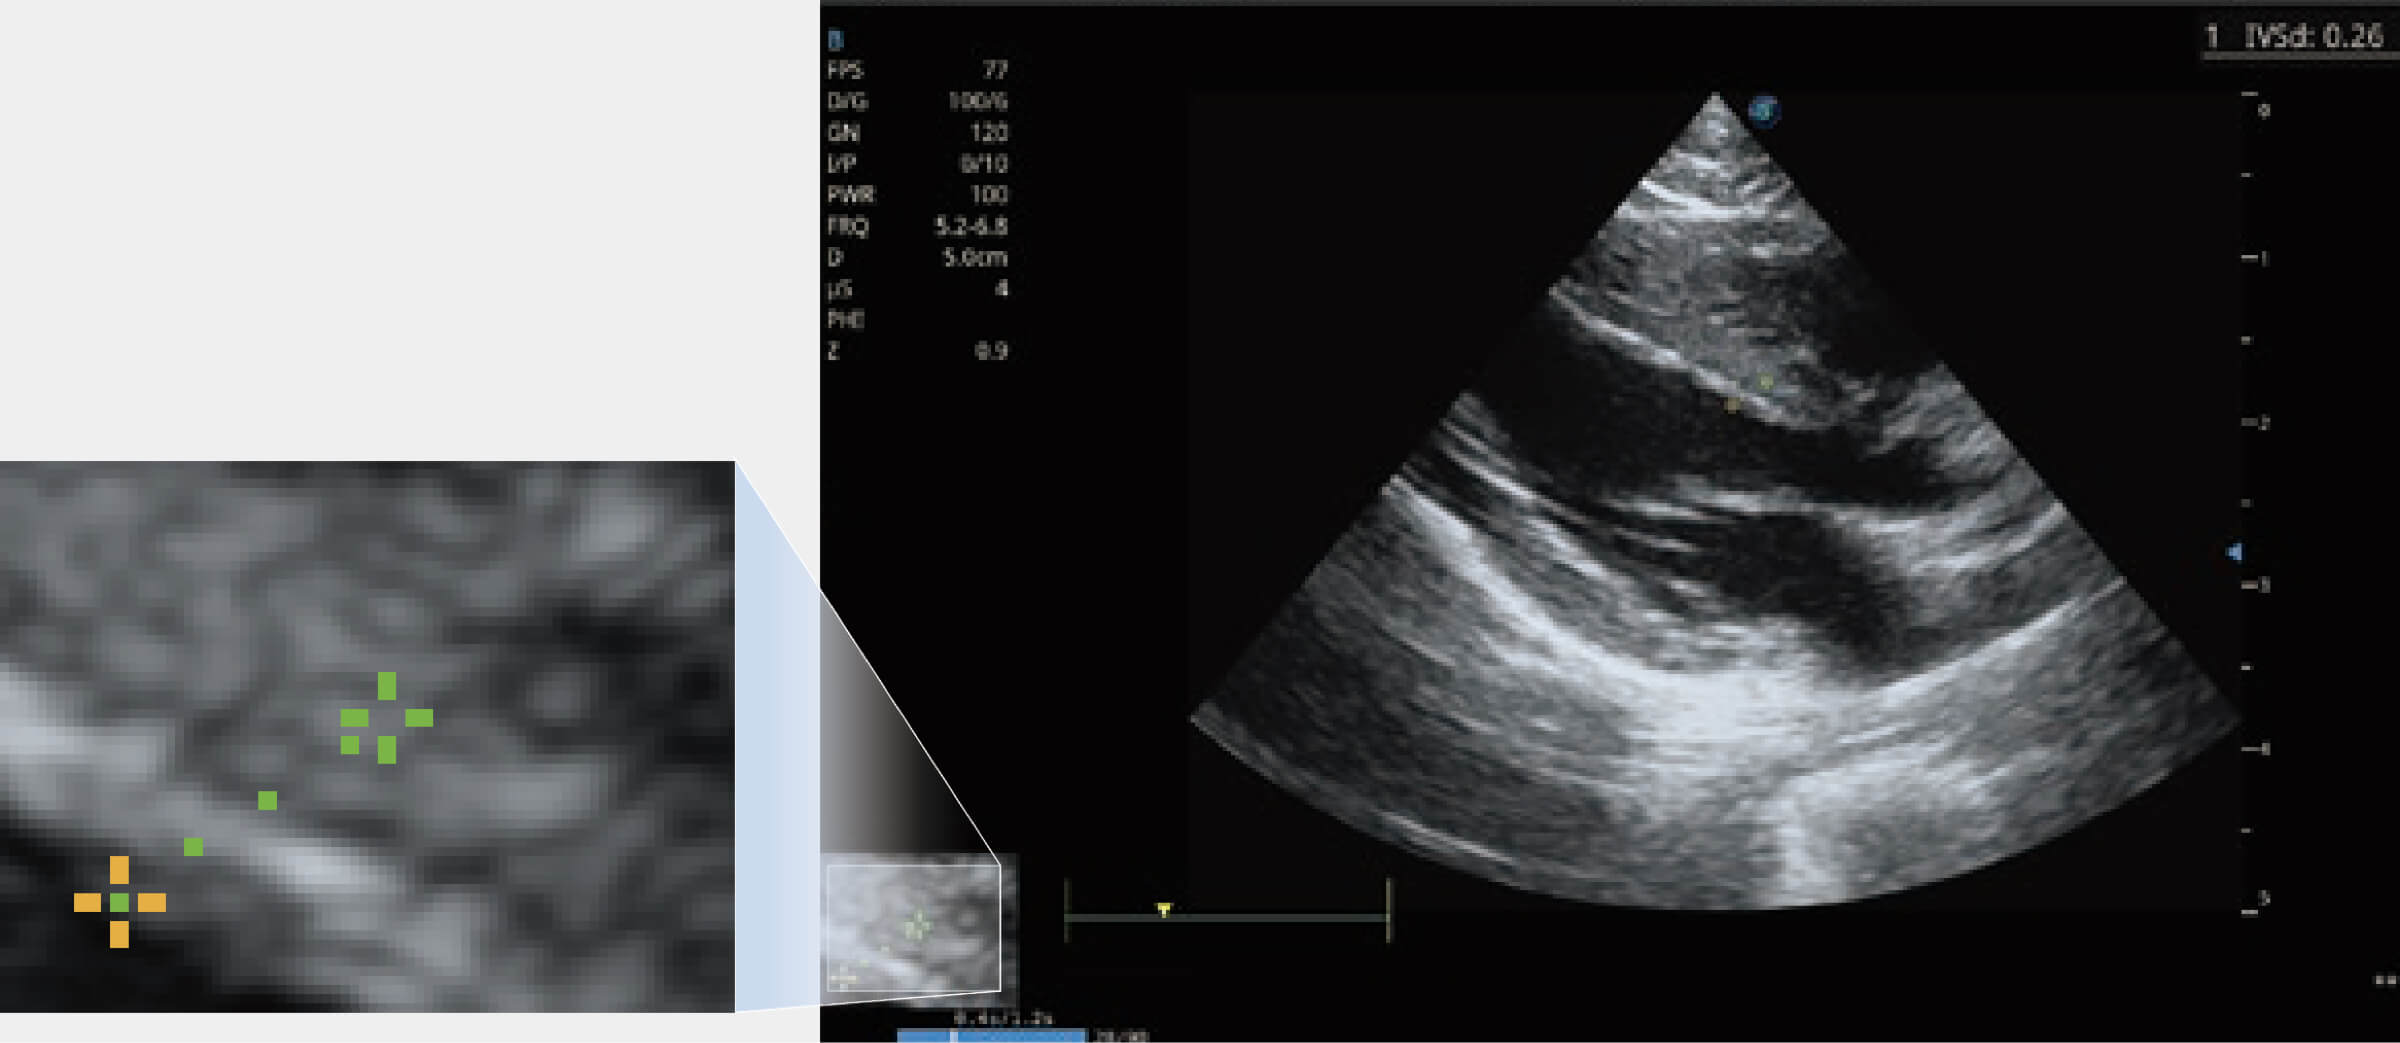

通過(guò)心肌識(shí)別技術(shù)與二維斑點(diǎn)追蹤技術(shù)相結(jié)合,對(duì)心臟的超聲圖像進(jìn)行量化分析。計(jì)算心肌17個(gè)節(jié)段的應(yīng)變、應(yīng)變率、速度、位移等,并通過(guò)牛眼圖的形式進(jìn)行呈現(xiàn)。